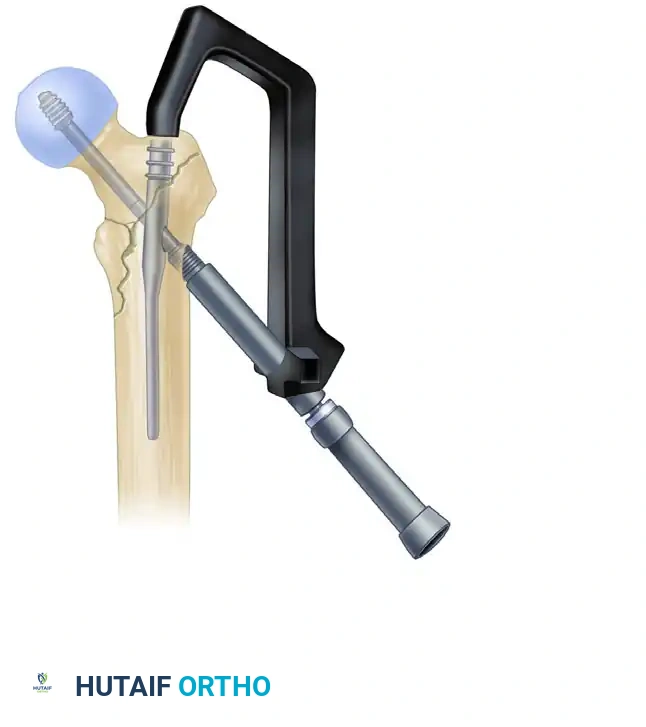

5. Lag Screw Placement and Compression

Achieving optimal lag screw placement is the most critical factor in preventing mechanical failure (cut-out). The goal is a Tip-Apex Distance (TAD) of less than 25 mm.

- Evaluate Version: Check the version of the nail on the lateral fluoroscopic view. The version is correct when the nail, the drill guide, the femoral neck, and the femoral head are all perfectly collinear.

- Make a small stab incision laterally through the skin and fascia lata corresponding to the targeting guide. Place the appropriate drill sleeve assembly down to the lateral cortex of the femur.

- Advance a threaded guide pin through the sleeve, up the femoral neck, and into the femoral head. Stop when the pin is within 5 mm of the subchondral bone.

- Confirm appropriate center-center position in the femoral head on both AP and lateral views.

- Measure for the length of the lag screw using the calibrated measuring device over the guide pin.

- Set the lag screw reamer to a depth 5 mm less than the measured length of the guide pin to prevent inadvertent joint penetration. Ream the lateral cortex and the lateral aspect of the femoral head.

- If the patient has dense, non-osteoporotic bone (e.g., a young patient with a high-energy mechanism), use a tap to prepare the thread path. In standard osteoporotic bone, tapping is generally unnecessary and may decrease screw purchase.

- Insert the lag screw over the guide pin until the threads are fully engaged in the subchondral bone of the femoral head.

- Use the centering sleeve insertion device to advance the centering sleeve over the lag screw shaft, locking it into the nail.

- Applying Compression: Before applying compression, release the traction on the fracture table. This allows the fracture fragments to settle. Insert the compression screw through the top of the nail and apply the desired amount of linear compression across the fracture site.